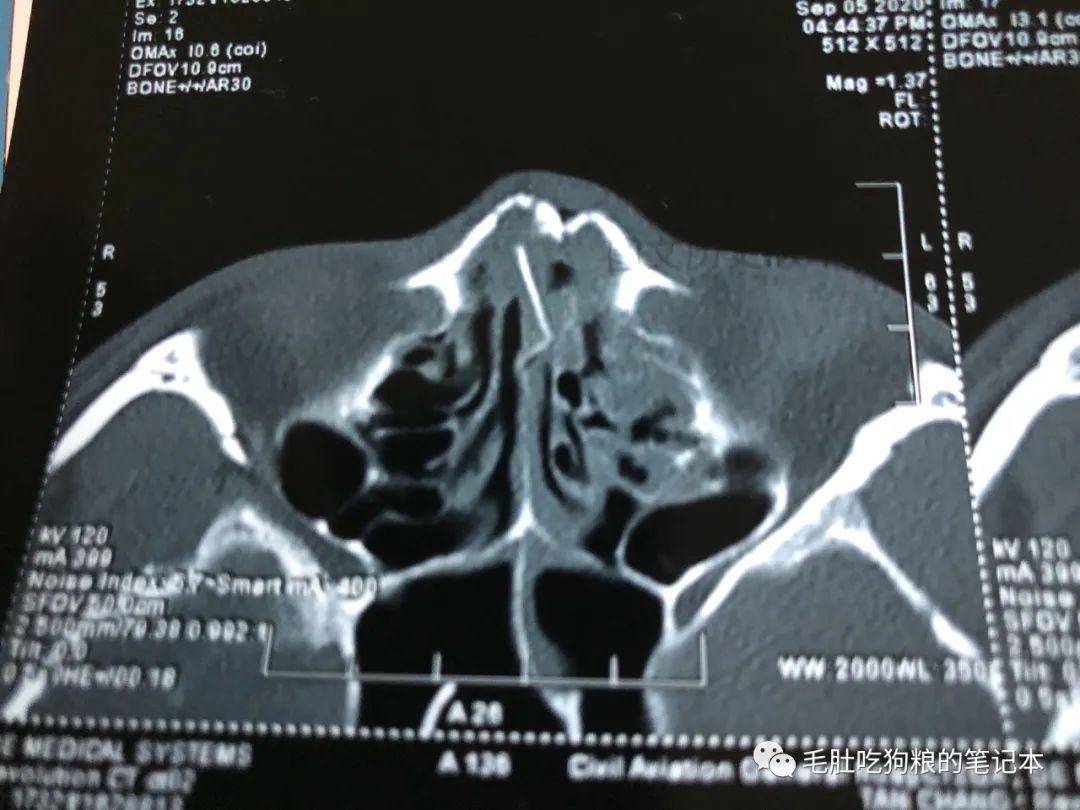

文末福利☞骨折的鼻骨